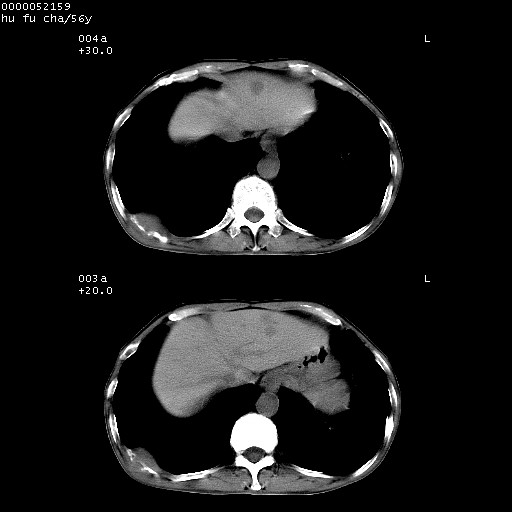

以下是引用zsl6918在2008-8-25 22:47:00的发言:[br]胸骨,胸椎及肋骨均可见多发转移表现,肝内低密度结节不除外转移。原发灶可能在右肺。双侧可见支扩表现。

以下是引用卜一在2008-8-26 8:02:00的发言:[br][br] 支持:肺癌并肺内,胸骨,胁骨,胸椎及肝内转移!另:左肺支气管扩张征伴感染! [br]

以下是引用zjzjr在2008-8-26 11:03:00的发言:[br]支持:肺癌并肺内,胸骨,胁骨,胸椎及肝内转移!另:左肺支气管扩张征伴感染!